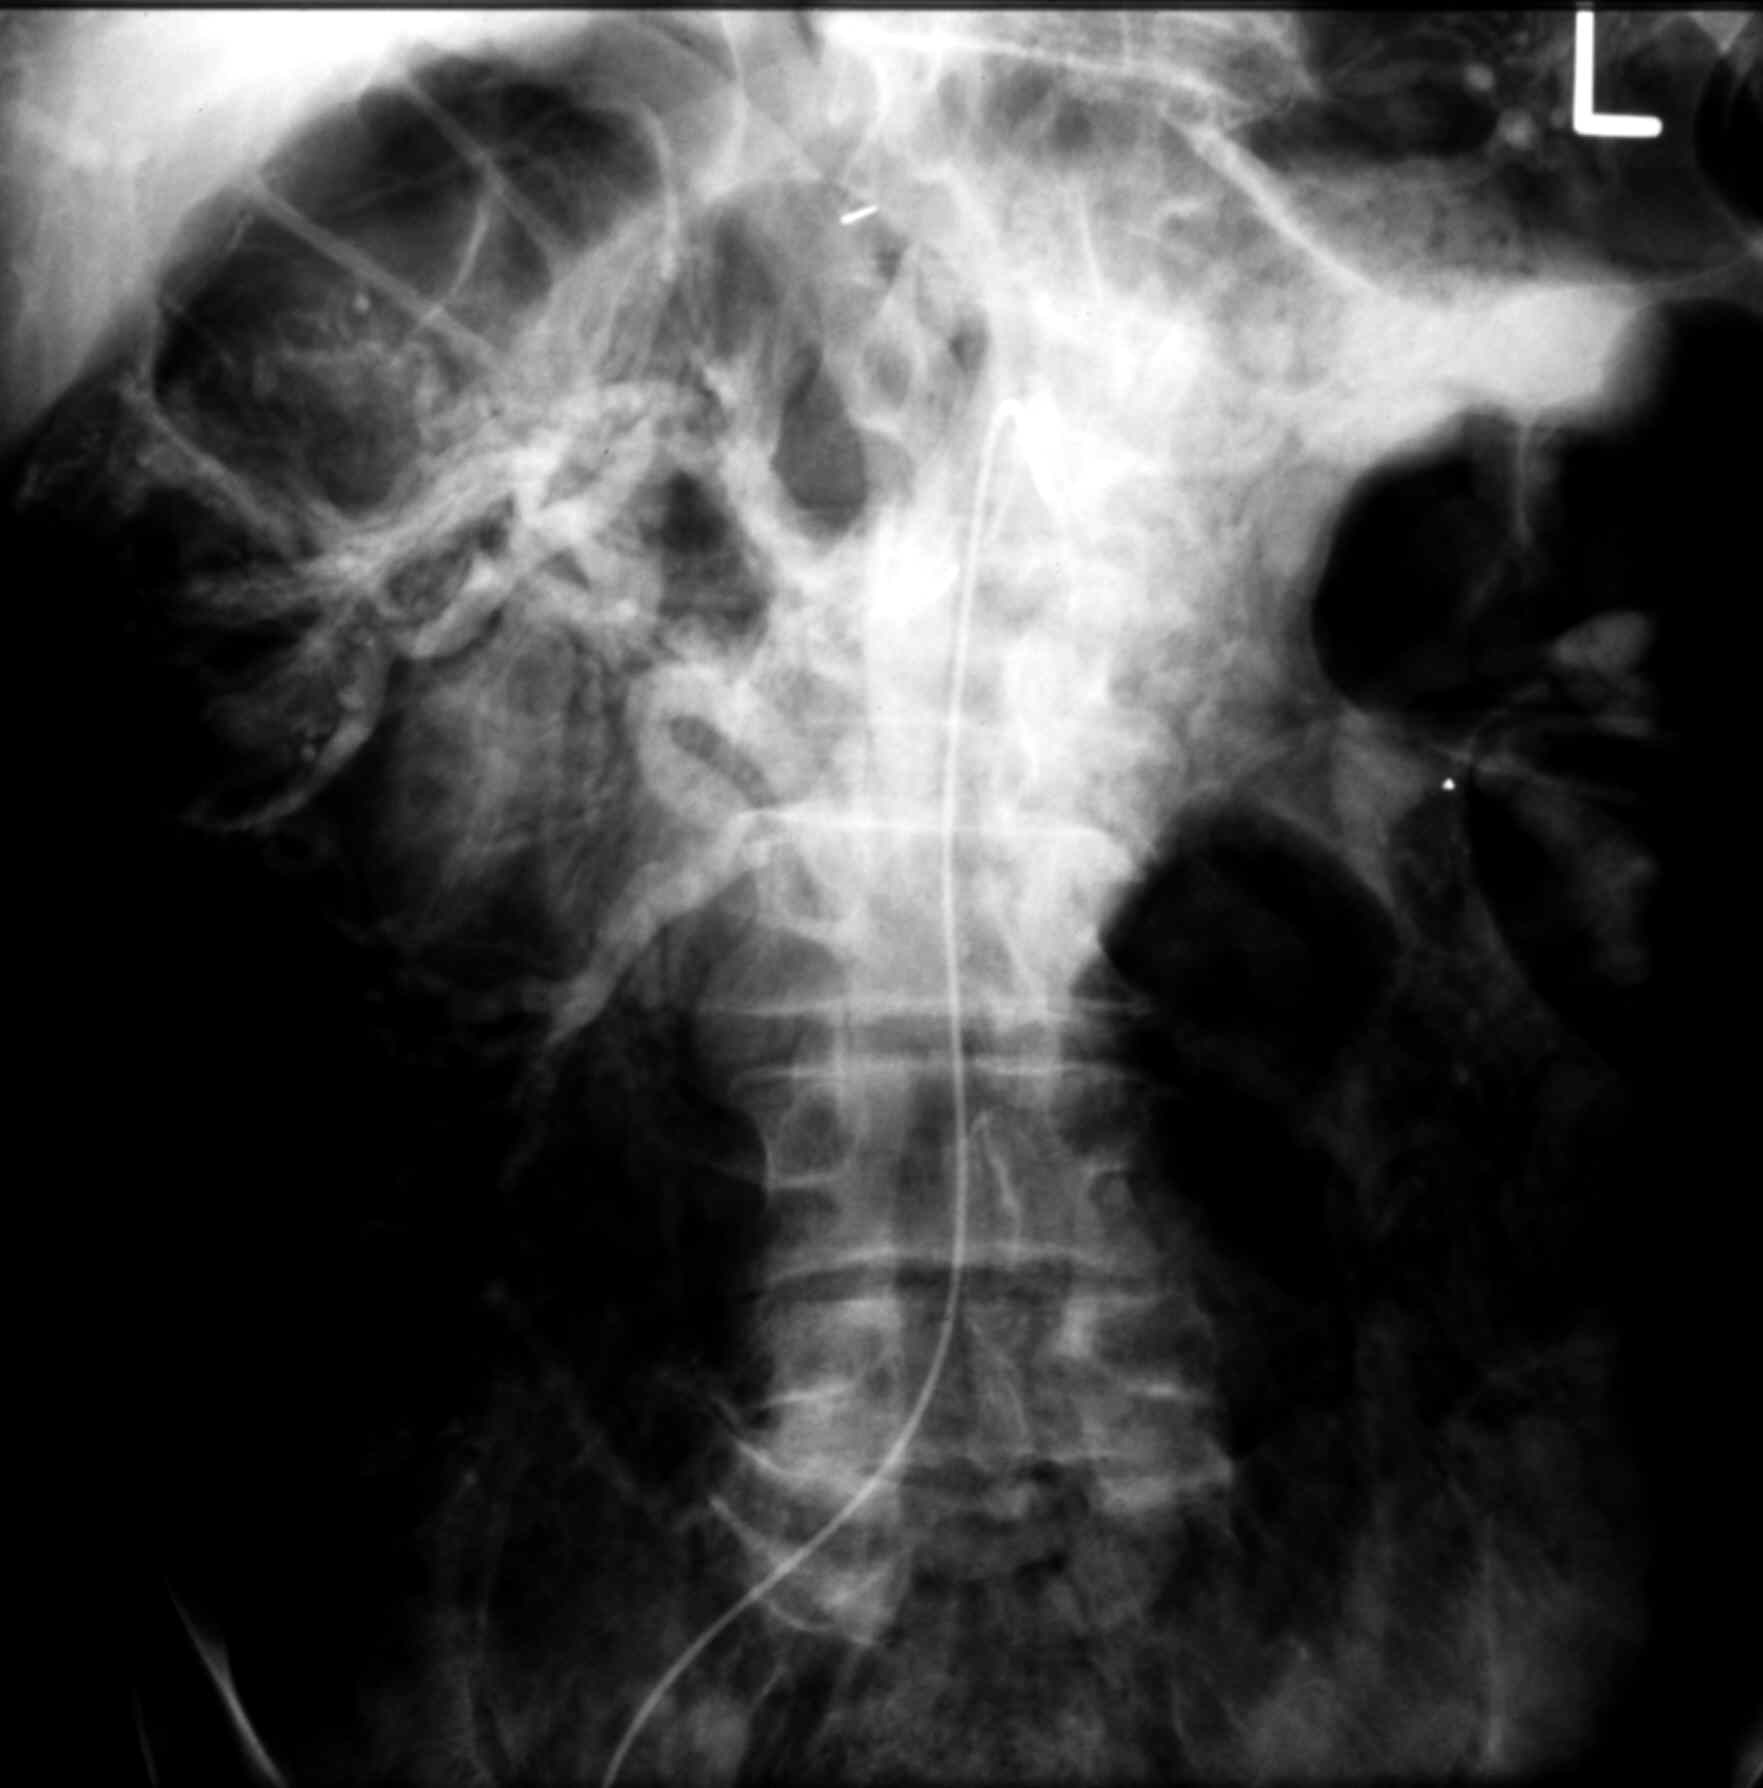

Radiology - MS I Normal Superior Mesenteric Arteriogram - Venous Phase

Identify: Superior Mesenteric V., Ileocolic V., Portal VV.